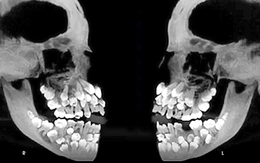

Ảnh X-quang cho thấy một người có 81 cái răng là thật

Tin đồn lan truyền kèm ảnh chụp X-quang cho thấy một người mắc chứng thừa răng có tổng cộng 81 cái răng.